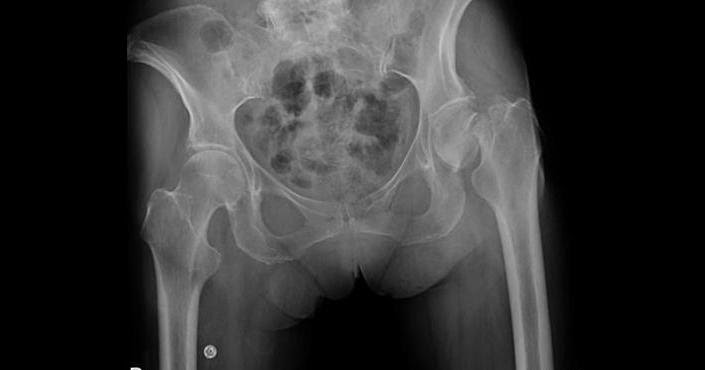

A hereditary condition in which failure of the resorptive mechanism of calcified cartilage interferes with its normal replacement by mature bone. Results in a symmetric, generalized increase in bone density

Osteopetrosis (Marble Bone)